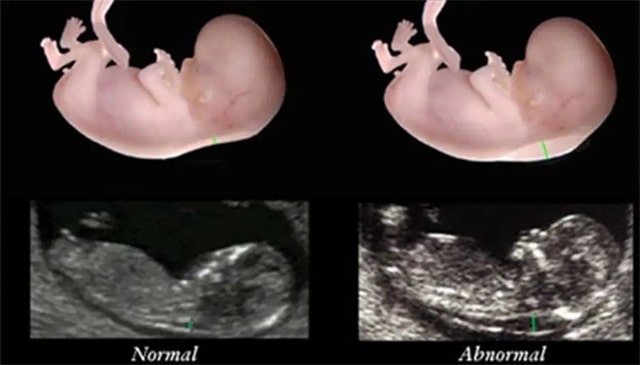

NT检查是孕早期非常重要的一次孕检,很多孕妈在第一次听到“NT”检查的时候,不知所云,一脸迷茫。

其实别看这个检查的名字由字母组成,有些“神秘”,其实NT检查就是一次特殊的B超检查,并没有大家想象中如此神秘。

在检查的过程中,B超医生会测量胎儿的颈后项透明层的厚度,以此来筛查胎儿患有唐氏综合征等染色体疾病的风险。

在做这项检查之前,孕妈们可以轻装上阵,无需忌口也无需空腹。每家医院对于NT正常值的标准可能会有略微的不同,大多数医院将3mm当成标准。如果胎儿的NT值大于3mm,则属于高风险。

即使胎儿的颈后透明层超标,也不一定证明胎儿有问题,孕妈们还需要做后续更多的筛查来判断。